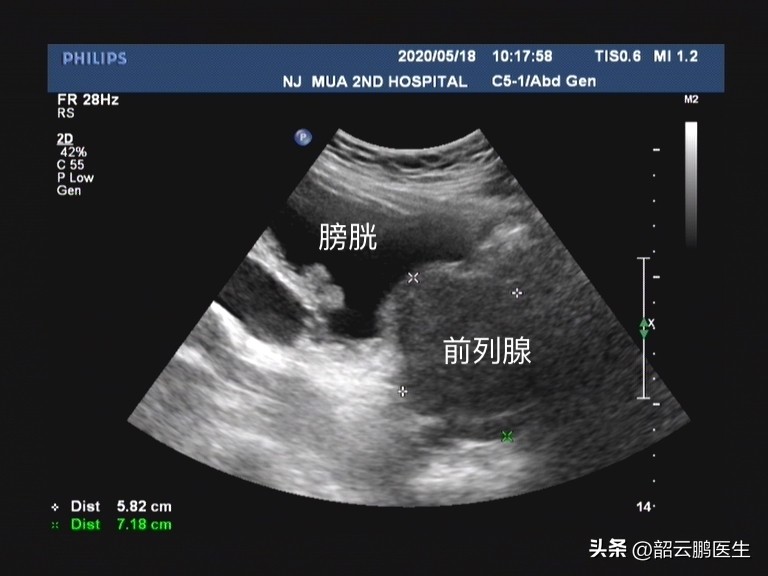

而评估临床进展性我们在临床上主要依靠 年龄、血清PSA、前列腺体积、最大尿流率、残余尿量、IPSS症状评分、前列腺慢性炎症、代谢综合征、膀胱内前列腺突入度 等一系列指标来评估。